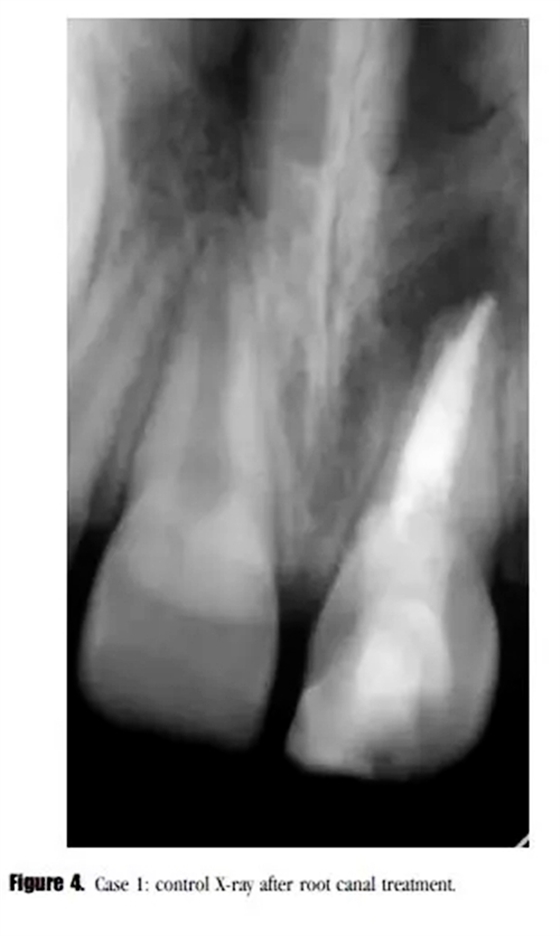

診斷為治療后的牙髓疾病復(fù)發(fā)。與患者家長商談,1個月后進行常規(guī)根管治療。根管內(nèi)使用 Total Fill RRM ( FKG Dentaire SA , La Chaux-de-Fonds , Switzeland )進行單尖充填(圖4)。

在3個月后的回訪中,患者癥狀消失,X線顯示根尖透射區(qū)域減小。(圖5)